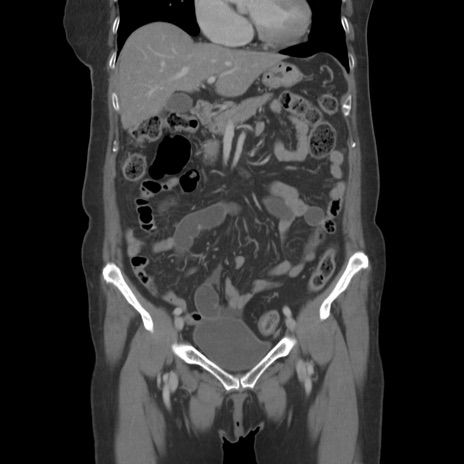

横断像

【症例】80歳代女性

【主訴】下腹部痛

【現病歴】約8時間前より下腹部痛の出現あり、救急外来受診。

【既往歴】両側付属器切除

【身体所見】意識清明、下腹部正中に手術痕あり、その部位に一致して圧痛と反跳痛あり。腸蠕動音は亢進。

【データ】WBC 9300、CRP 0.15